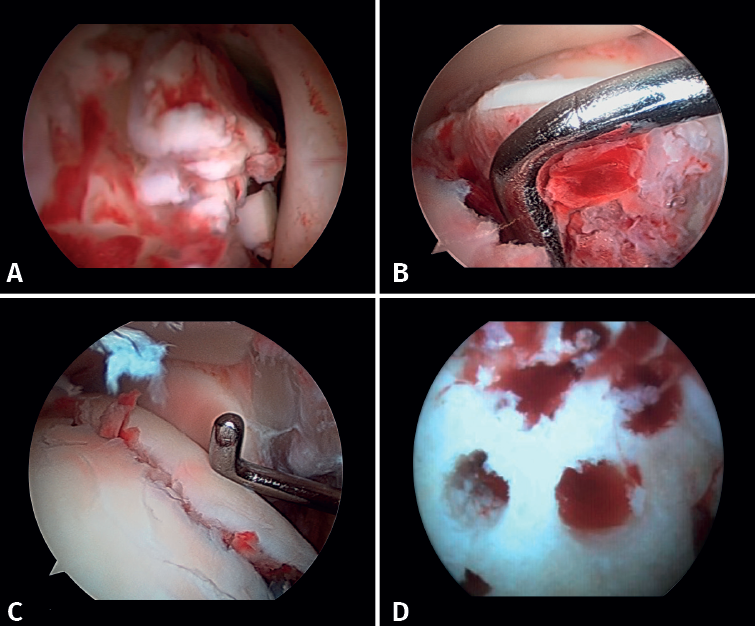

- Management of chondral injuries. The literature reports the presence of chondral injuries in 34-91% of all ankle fractures. These lesions are frequently located in the talus and are most common in severe fractures, such as Weber C and PER fractures. Patients with cartilage lesions were 3.5 times more likely to develop radiographic osteoarthritis (Kannus arthritis score < 90) and 5 times more likely to have an unfavorable long-term clinical prognosis (American Orthopedic Foot and Ankle Society [AOFAS] score < 90)(14).

If possible, we reinsert unstable osteochondral fragments (Figure 3). In chondral lesions where it is not possible to reinsert the fragment, cartilage repair stimulation techniques can be used(5,13).

Figure 3. A: loose bodies; B: osteochondral lesion; C: reduction of the osteochondral lesion; D: medullary stimulation.